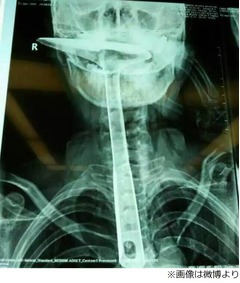

緊急搬送された病院の検査では、"フライ返し"の取手部分はすべて陳さんの喉から胸のあたりにまで侵入していた。先端部分だけが口から出ているという有様で、食道の粘膜の損傷が激しく、右肺は膨張不全の状態に陥っており、その日の晩から2度にわたる大手術が行われることになった。

最初の手術では食道を拡張して"フライ返し"を引き抜こうとしたが、胸の食道部分の損傷が激しく、頸部のみの食道を残すようにして残りのすべてを切除。そのため、2回目の手術ではいかに陳さんの摂食問題を解決するかに焦点が当てられた。こちらは食道がんの患者同様に食道胃形成術が施され、陳さんは窮地から何とか"復活"を遂げることができたのだという。